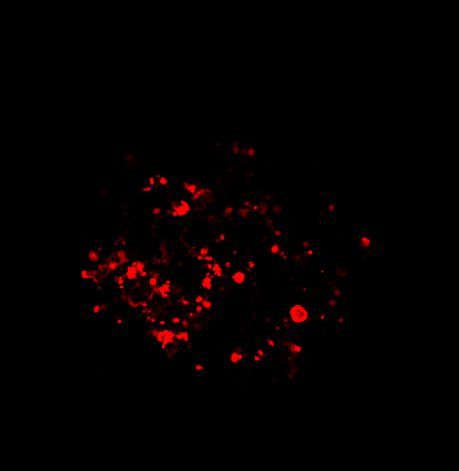

图 A:使用 20 倍空气物镜(顶部)和 25 倍硅油物镜(底部)获得的肿瘤球体 Z 堆栈的最大密度投影 (MIP)。活细胞用钙黄绿素(绿色)标记,死细胞用 PI(红色)标记。细胞核用 Hoechst(蓝色)染色。比例尺:100 um。这些图像是使用 CrestOptics X-Light V3 转盘获取的。

图 C:使用 20 倍空气物镜(左)和 25 倍硅油物镜(右)获得的球体的 3D 体积视图。活细胞用钙黄绿素(绿色)标记,死细胞用 PI(红色)标记。细胞核用 Hoechst(蓝色)染色。沿 Z 轴的比例尺:120 um。这些图像是使用 CrestOptics X-Light V3 转盘获取的。